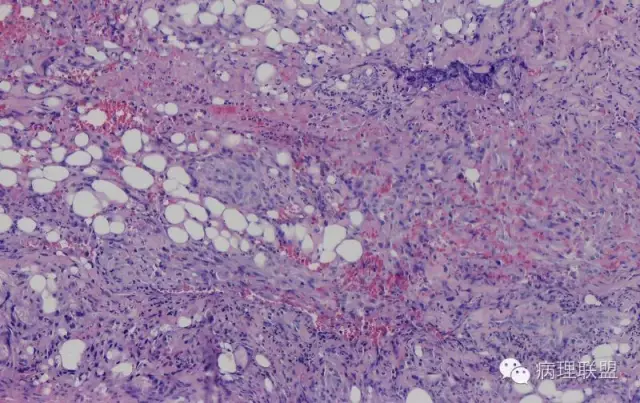

@南方医科大学病理梁莉 形态较符合复合性血管内皮瘤(composite hemangioendothelioma),属中间性血管性肿瘤。此肿瘤尽管多见于成人,也可发生于婴幼儿。

@南方医科大学病理梁莉 我开始也考虑这个,但仔细看不是太符合。

而复合性血管内皮瘤则是由良性、中间性和恶性的成份组成,也是浸润性生长,常常侵犯皮下脂肪组织,此例细胞形态由梭形细胞、卵圆形细胞及上皮样细胞组成,形态可见良性区域、中间性区域及高分化血管肉瘤或上皮样血管肉瘤区域,因此,似乎复合性血管内皮瘤更妥。此类肿瘤可以发生于婴幼儿。当然与Kaposi型血管内皮瘤一样,同属中间性血管瘤,只是后者,若肿瘤体积大,可出现Kasabach-Merritt综合征。

个人觉得应该是皮下纤维素渗出导致的内皮细胞旺炽性增生,局部呈内皮细胞乳头状增生,不认为是迷路样吻合;可能是婴幼儿血管瘤破裂诱发,也可能是血管畸形诱发。

注意活跃增生的内皮细胞总是与纤维素关系密切,并非穿插浸润的真皮胶原束。

混合型血管内皮瘤虽是混合各种形态,但是其主要成份一定是内皮瘤成份,上皮样血管内皮瘤或网状血管内皮瘤成份,其它血管肉瘤,血管瘤次要。@广医二院_病理科_梅开勇 仔细看了,好像是胶原。